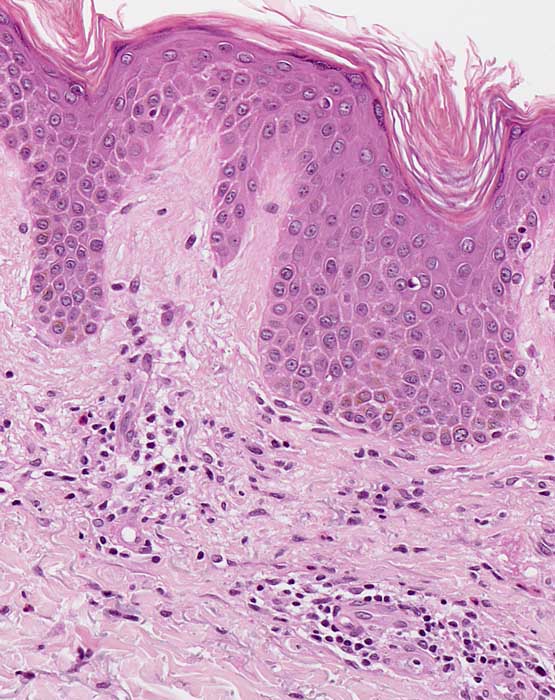

Kompakte Hyper-Orthokeratose. Unregelmässige psoriasiforme Epidermishyperplasie und diskrete Spongiose. Oberflächlich dermales perivaskulär betontes Entzündungsinfiltrat mit Beteiligung einzelner eosinophiler Granulozyten. Geringe Fibrose der papillären Dermis.

Chronische Kontaktdermatitis.

Histologie

200